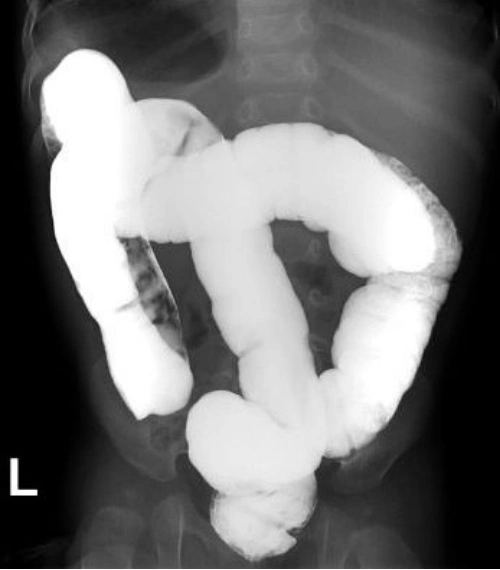

术前钡灌肠造影提示肠扭转

肠扭转

急腹症的外科处理系列之乙状结肠扭转_医学界-助力医生临床决策和职业